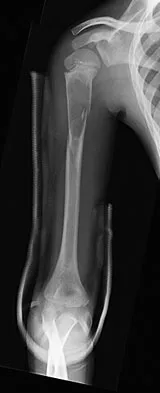

An 11-year-old boy has right shoulder pain and has been unwilling to use the arm after throwing a baseball in a Little League game 3 weeks ago. Examination reveals upper arm and shoulder tenderness with swelling. A radiograph and MRI scan are shown in Figures 27a and 27b. Management should consist of

Explanation

The radiograph is consistent with a unicameral (simple) bone cyst. The MRI scan reveals that the cyst is juxtaposed to the physis and therefore can be classified as active (latent cysts are more than 1 cm away from the physis). Active cysts are treated with aspiration and steroid injection, although repeated injections may be necessary. Curettage and bone grafting results in more reliable healing but may lead to growth arrest in active cysts. Iannotti JP, Williams GR: Disorders of the Shoulder: Diagnosis and Management, ed 1. Philadelphia, PA, Lippincott Williams & Wilkins, 1999, pp 945-946.